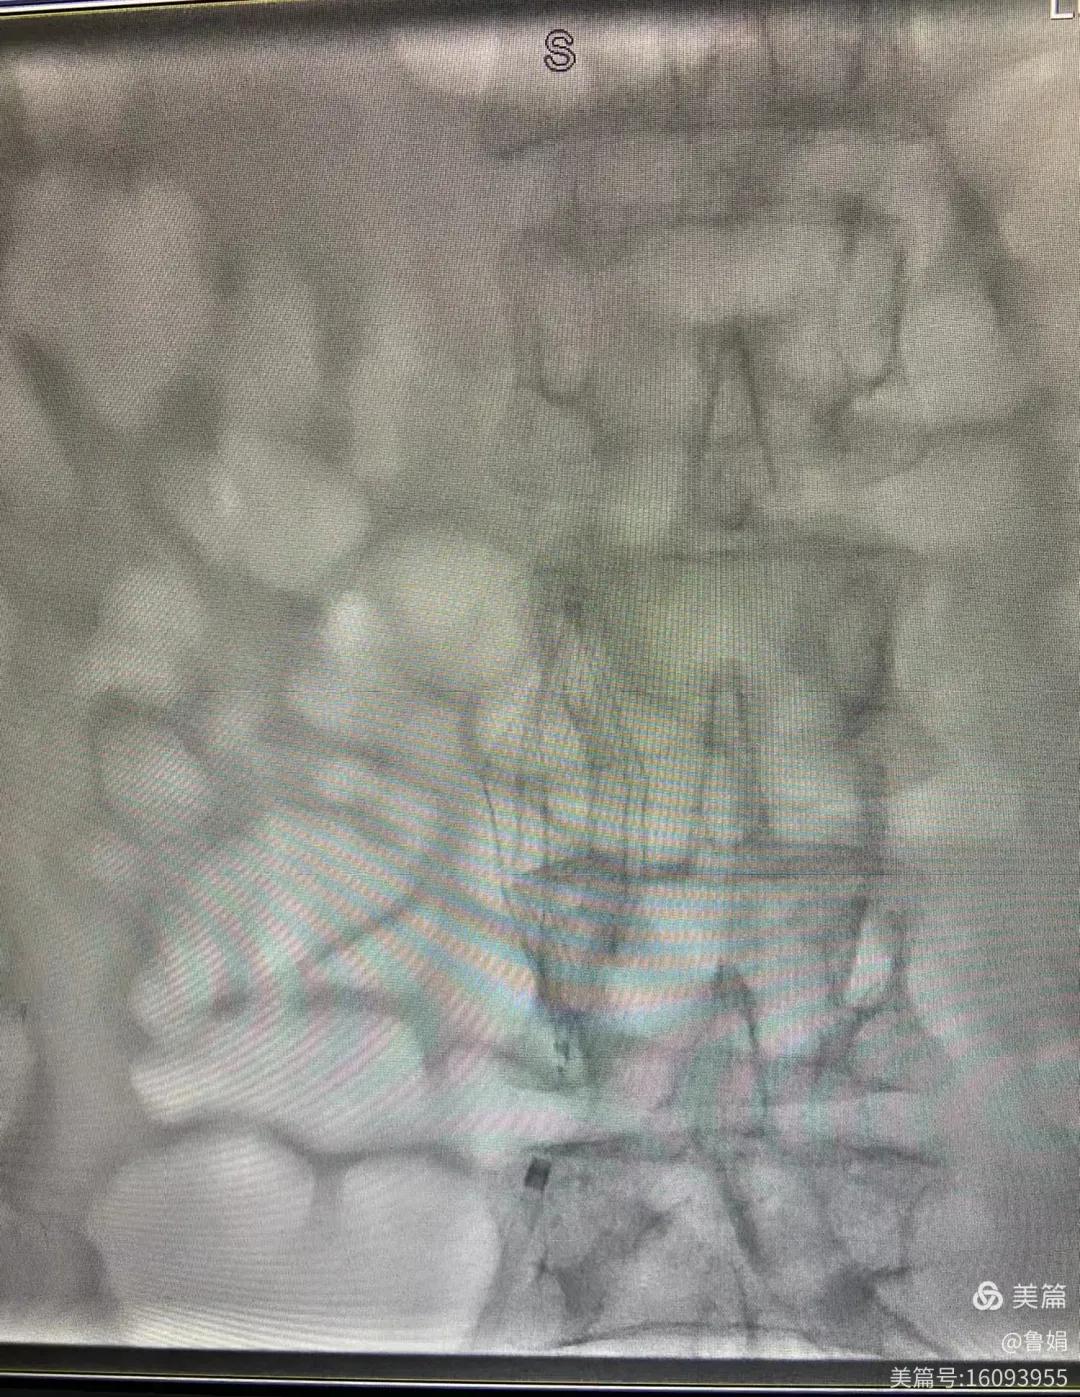

11月3日,漯河市中醫(yī)院血管外科副主任周創(chuàng)業(yè)與腦二科介入醫(yī)生孫亞中,兩位醫(yī)生為一位腦梗死伴下肢深靜脈血栓形成患者成功開展下腔靜脈濾器置入術(shù)。

圖片術(shù)后濾器順利植入

經(jīng)認(rèn)真查看患者病例,探討患者病情及術(shù)中潛在風(fēng)險因素,多科會診后急診為患者開展介入手術(shù),術(shù)中周創(chuàng)業(yè)副主任、孫亞中副主任中醫(yī)師二人通力合作,手術(shù)順利,病人術(shù)中出血少,生命體征平穩(wěn),現(xiàn)在腦二科病房繼續(xù)對癥治療。(介入中心:魯娟)